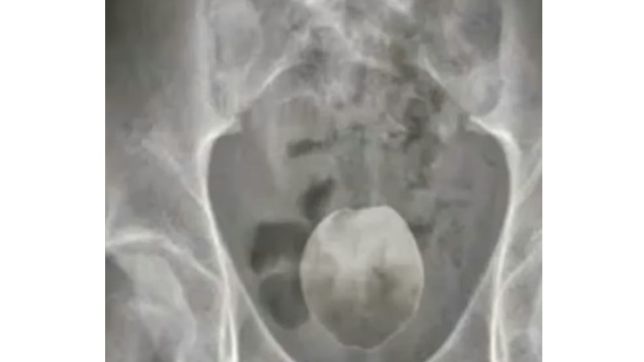

Um homem de aproximadamente 50 anos precisou ser internado após dar entrada no Pronto Atendimento Municipal com fortes dores abdominais. Após exames, foi constatada a presença de um coco verde introduzido no reto, o que causou uma grave obstrução intestinal.

Segundo informações divulgadas por portais locais, o fruto tinha aproximadamente o tamanho de uma mão e precisou ser removido cirurgicamente no Hospital São Lucas, para onde o paciente foi transferido. O procedimento foi bem-sucedido, e o homem permanece em observação hospitalar, com quadro clínico estável. Sua identidade não foi divulgada.